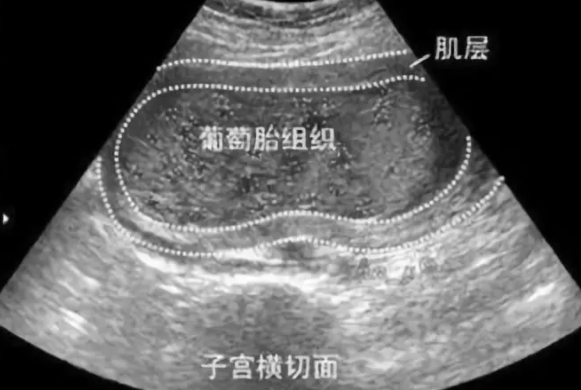

容易葡萄胎的三種女性:葡萄胎浸入子宮肌層或在其它部位發(fā)生轉(zhuǎn)移,稱為“惡性葡萄胎”。 惡性葡萄胎多數(shù)在葡萄胎清除后6個(gè)月內(nèi)發(fā)生,但亦有葡萄胎未排出之前就發(fā)生惡變者。惡性葡萄胎的真正發(fā)生原因,專家都還不怎么清楚,但是醫(yī)學(xué)上有很多解釋,比如胚胎死亡,營養(yǎng)因素,病毒因素等,但是它跟染色體有關(guān)。